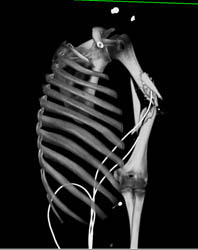

Stent in Subclavian Artery